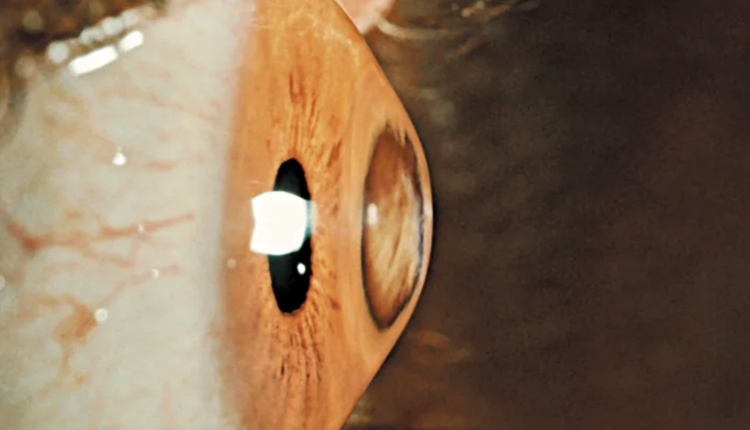

Η εν λόγω νόσος είναι ο κερατόκωνος, κατά τον οποίο παρατηρείται παθολογική λέπτυνση του κολλαγόνου στον κερατοειδή χιτώνα του οφθαλμού. Η λέπτυνση προκαλεί αστάθεια και αλλαγή του σχήματος του κερατοειδούς, ο οποίος από σχεδόν σφαιρικός γίνεται κωνικός.

Ο κωνικός κερατοειδής έχει πολύ λεπτό πάχος, καθώς μειώνεται κεντρικά από τα φυσιολογικά 550 μικρόμετρα (μm) μέχρι και 300 μm. Το μικρόμετρο (ή μικρόν) ισούται με ένα εκατομμυριοστό του μέτρου. Ο κωνικός κερατοειδής έχει επίσης σημαντικά παραμορφωμένη πρόσθια και οπίσθια επιφάνεια.

Οι αλλαγές αυτές προκαλούν μη ομαλή και σημαντικά αυξημένη κυρτότητα, συνήθως παράκεντρα. Αυτό δημιουργεί συνήθως μυωπία και σημαντικό αστιγματισμό. Ένας τέτοιος κερατοειδής έχει ως αποτέλεσμα η διάθλαση του φωτός στον οφθαλμό να είναι ανώμαλη και το είδωλο να είναι πολύ ασαφές (διπλό, πηγές φωτός με «ουρές»).